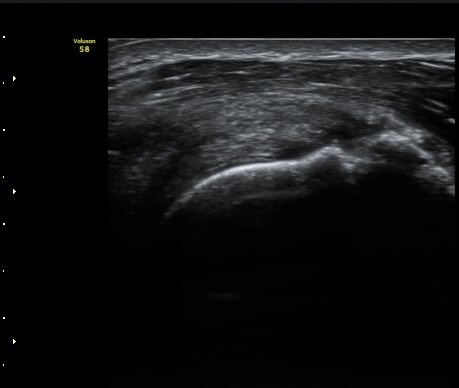

ÆÈÀ» ¿ÜȸÀüÇÏ´Ï °ß°©ÇÏ±Ù°Ç Ç¥ÃþÀÇ ¼ö¾×Àú·ù°¡ ´õ¿í È®½ÇÇÏ°Ô °üÂûµµ´Ï´Ù(»çÁø 4).